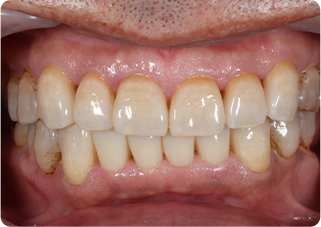

セラミッククラウン症例①

術前

仮歯

技工物

術後

| 主訴 | 見た目を綺麗にしてほしい |

|---|---|

| 治療期間/回数 | 3ヵ月、5回 |

| 価格(税込) | 363,000円(税込) |

| リスク・副作用 | セラミック破損の可能性 |

| ポイント | 自然な色、形となるようにオーダーメイドでセラミックを盛ってクラウンを作製した。 |